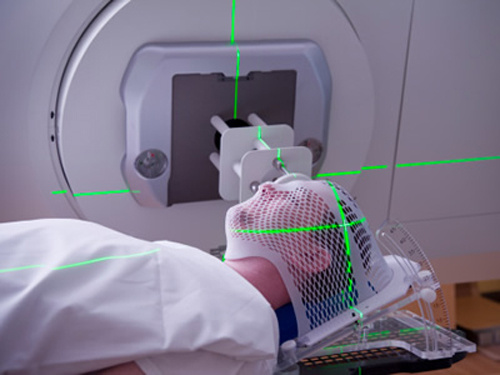

(1)药物治疗:糖皮质激素治疗、贝伐珠单抗、脱水降颅压药物、脑保护治疗药物、自由基清除剂、高压氧治疗。

(3)手术治疗:目前手术治疗被认为是放射性脑损伤治疗中的最后一步。主要针对积极内科保守治疗无效、囊性变或者脑水肿等占位效应明显、颅高压症状或者相应神经功能障碍进行性加重的患者。